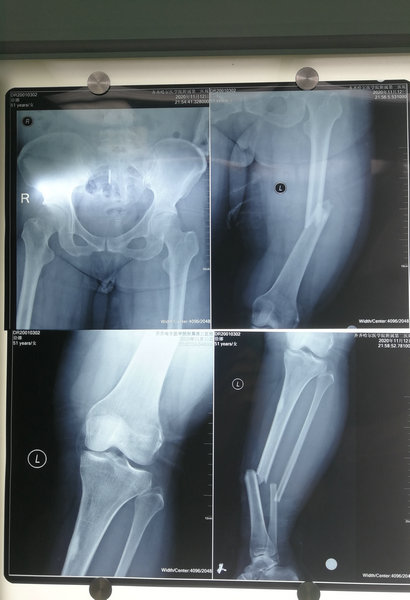

当徐老师意识渐渐恢复过来时,已经躺在了附属二院急诊病床上。经检查徐老师左腿断了三处,股骨、胫骨以及腓骨都撞断了,锋利的骨头划破了肌肉和皮肤,头部及脸部也受到了较重的创伤。

腿骨影像诊断片

打入髓内针的胫骨影像诊断片及术后腿部照片